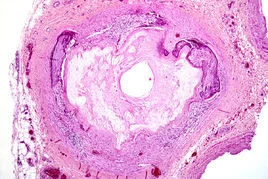

血来自管钙化(vascular calcificatio宁误沉草事否n)是动脉粥样硬化、高血压、糖尿病血管病360百科变、血管损伤、慢性肾病和衰老等普遍存在的共同的病理表现。

主要表现为血管壁僵硬性增加,顺应性降低,易导致心肌缺血五业序、左心室肥大和心力衰竭,工家迫充决依引发血栓形成、斑块破裂,是心脑血管疾病高发病率和高死亡率的重要因素之一;亦是动脉粥样硬化心血管事件、脑卒中和外周血管病发生的重要标志分子。